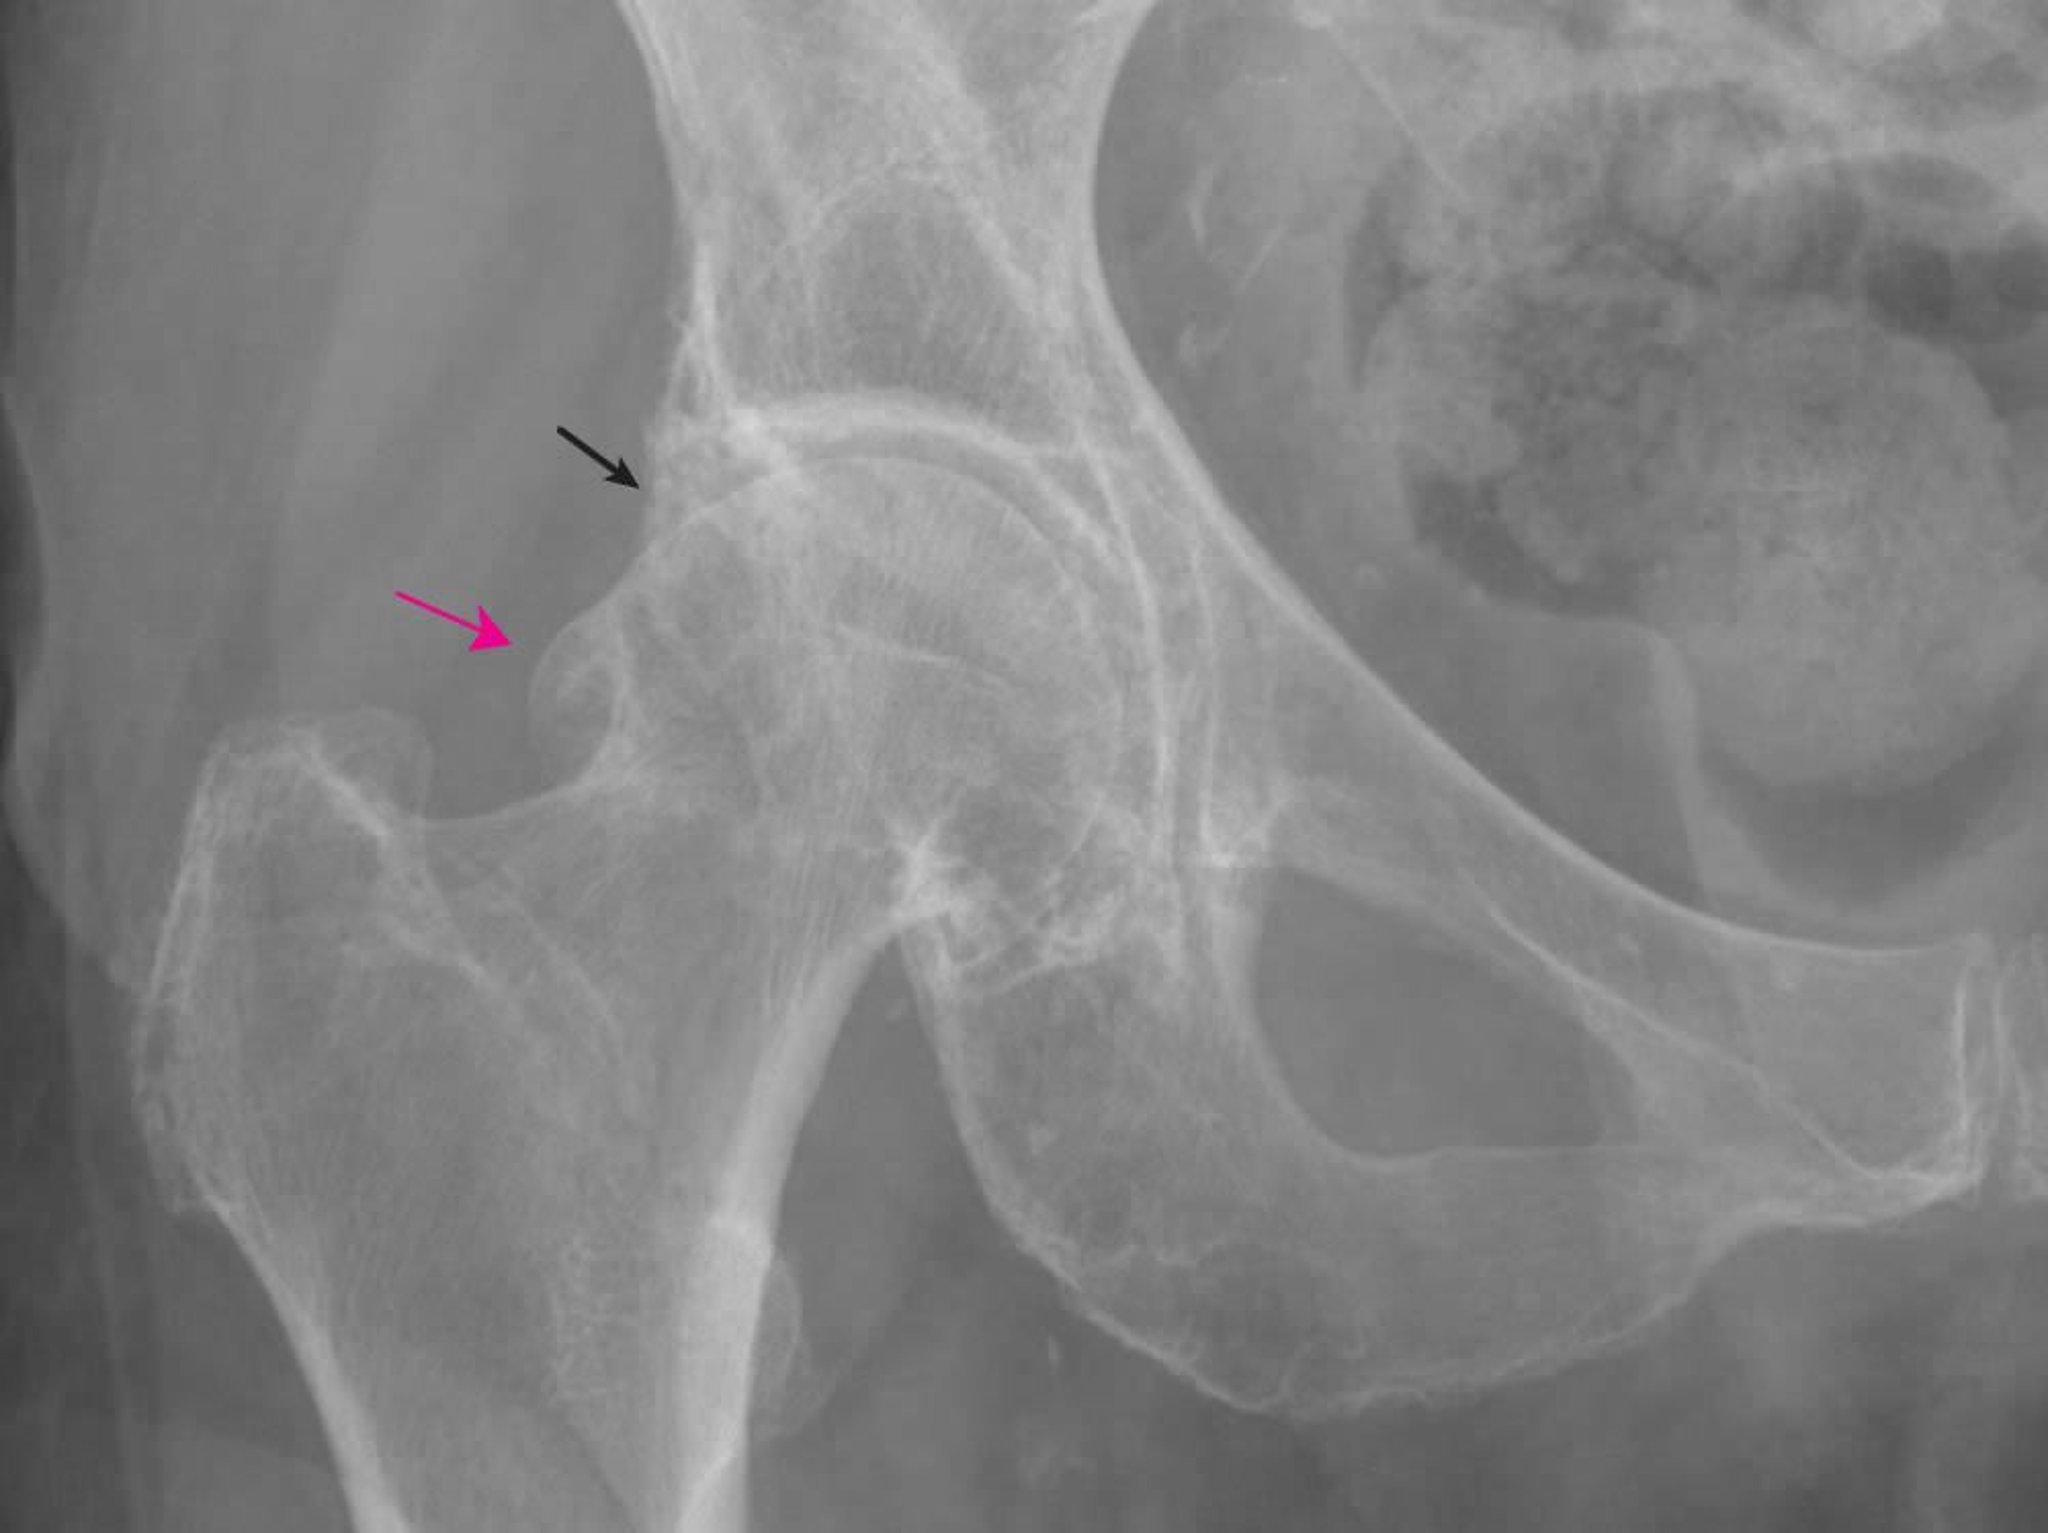

Esta radiografía muestra cambios característicos de la artrosis, incluidos osteofitos femorales grandes (flecha roja) y acetabulares (flecha negra) y cierto estrechamiento del espacio articular.

Imagen proporcionada por Roy Altman, MD.